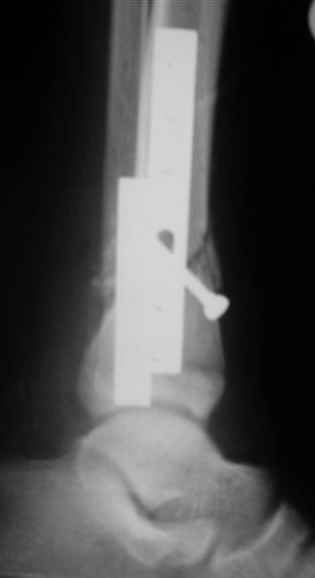

Помятуя наш недавний разговор о фиксации м.б. кост, высылаю послеоперационные картинки..

Напомню- разбирали случай 17 летнего молодого человека перелом дист тиб.фиб. хирургия после 3 недель с момента травмы( безуспешные попытки закрытой репозиции) Раны заживают первичным натяжением, занимается физиотерапией, пока никаких проблем не наблюдается

Согласный я с тобой:-)) есть остаточная вальгусная деформация (по снимку видно перекрывание дист. фрагментом б.б по латеральной поверхности проксимальноо фагмента на 2-3 мм и наружная лодыжка репонирована с укорочением, судя по прямой проекции. Необходимость использования интраоперационно дистрактора была бы оправдана (вручную было непросто *вытянуть* дистальный отломок.)